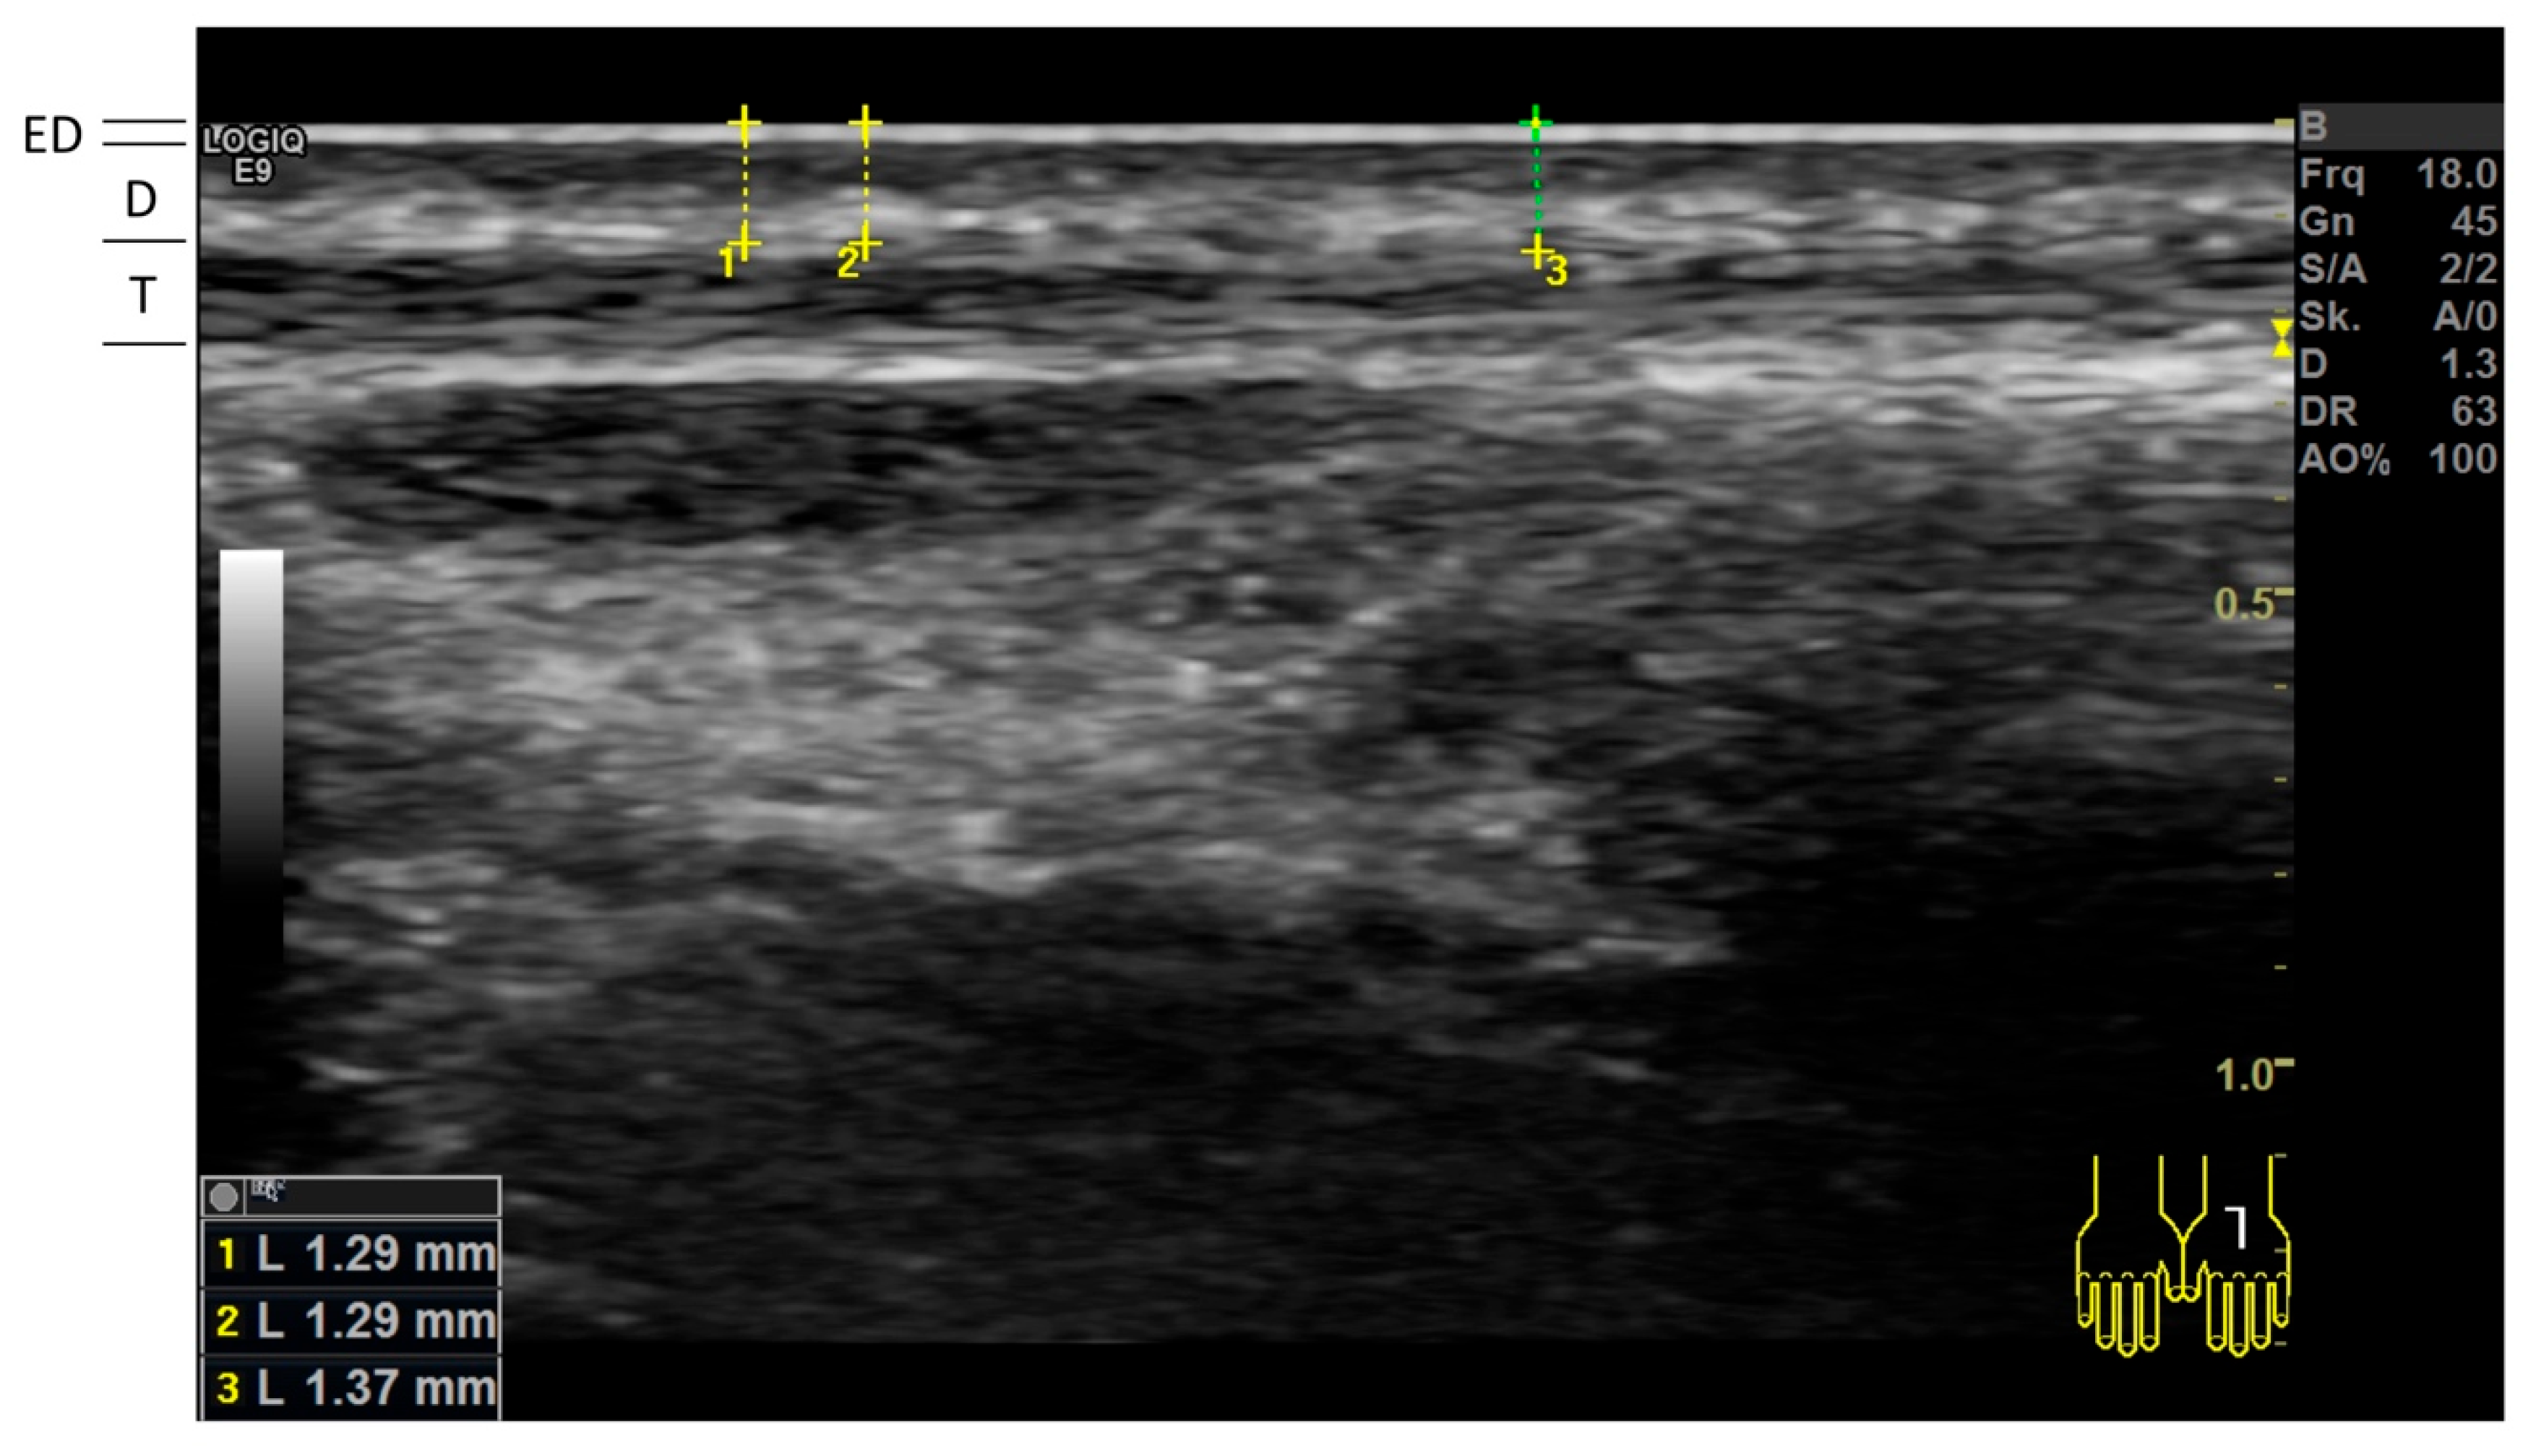

2.4. High-Frequency Ultrasonography (HFUS)

| Cutis thickness measured by HFUS (mm) | n = 53 | n = 53 | |

| Back of hand | |||

| mean (±SD) | 0.66 (±0.12) | 0.82 (±0.18) | <0.001 |

| Cubital fossa | |||

| mean (±SD) | 0.86 (±0.15) | 1.00 (±0.21) | <0.001 |

| Dorsal midfoot | |||

| mean (±SD) | 0.76 (±0.16) | 0.94 (±0.18) | <0.001 |